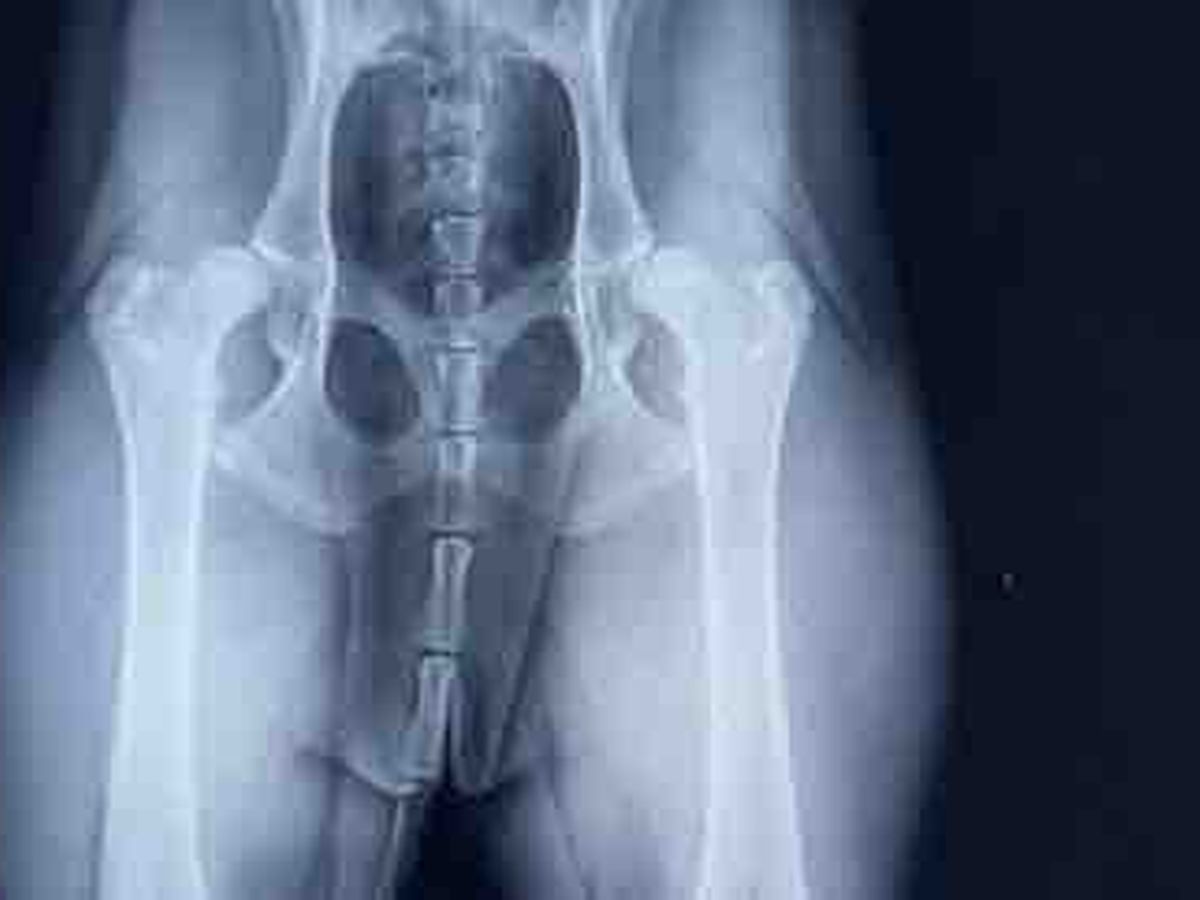

Hi everyone, my name is Jessica and I’m fundraising for a sweet young mixed breed dog named margarita. This poor girl is so young at only 11 months old she still has her whole life ahead of her. Margaritas mom noticed her hips weren’t growing properly like her front shoulders she would always walk on her back tippy toes keeping her hips together and she would yelp periodically from pain. After taking her to duck creek veterinary hospital in Smyrna Delaware and receiving X-rays she was given the awful news that margarita was born with severe hip dysplasia and neither ball on either hip sits in the correct place in the socket. Unfortunately the only fix is a double hip replacement at a special orthopedic surgeon in Annapolis Maryland costing $7000 dollars. This poor rescue pup is so young and sweet and doesn’t deserve to be in this much pain everyday. Any donations large or small will help and are greatly appreciated. Donations can also be made to Dr . Shonts at duck creek animal hospital at [phone redacted] as she is also trying to get the word out to raise money for margarita.